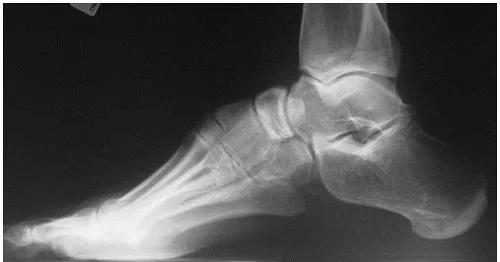

A cavus foot is characterized by an excessively high arch that persists during weight bearing. This abnormal alignment shifts weight toward the heel and forefoot, increasing pressure in these areas and reducing the foot’s ability to absorb shock.

Weight-bearing X-rays are typically used to confirm the diagnosis and evaluate alignment, joint relationships, and associated deformities. Advanced imaging or neurologic evaluation may be considered when an underlying condition is suspected.